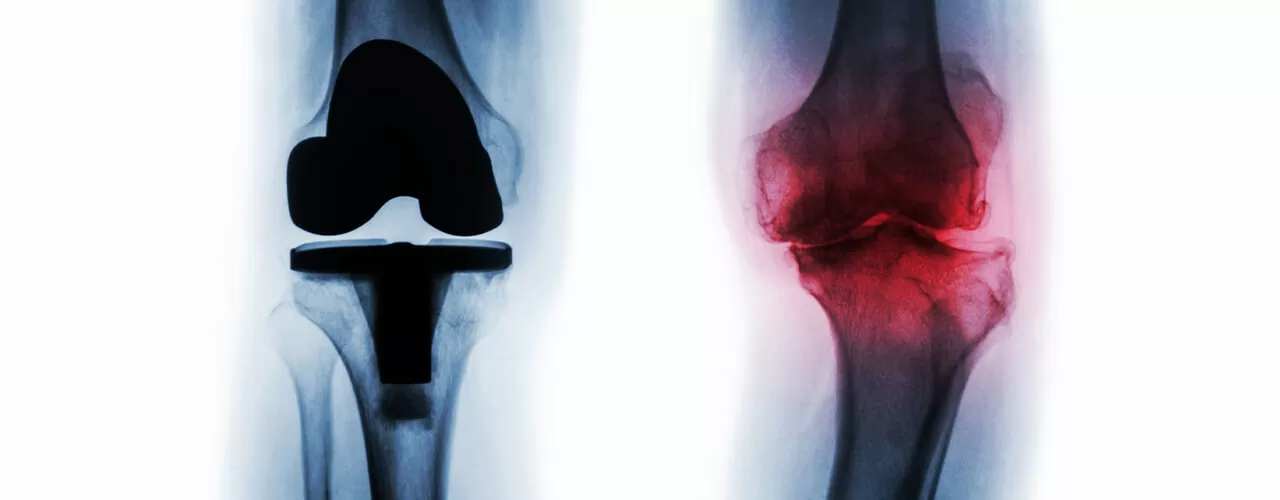

If you have received a total joint replacement of the knee, hip, or shoulder, physiotherapy can benefit you. Our Edmonton, AB clinics provide joint replacement physiotherapy rehabilitation to those whose mobility is limited due to a replacement procedure, or even those who experience impairing joint pain without having gone through replacement surgery yet. If your joints are a constant source of pain, Stride Sports & Physiotherapy can help provide you with some relief.

- Have severe joint damage. This is typically due to arthritic debilitation, either from osteoarthritis or rheumatoid arthritis.